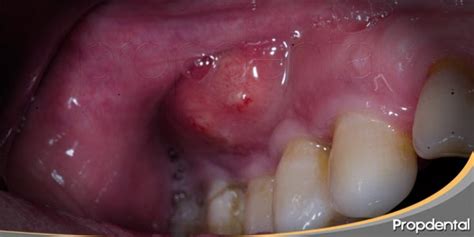

Un absceso es una infección bucodental que se manifiesta por la aparición de pequeñas bolsas de pus en diversas zonas del diente. Suelen ser muy molestos y, en ocasiones, pueden causar un dolor de dientes insoportable. Existen varios tipos de abscesos dentales:

- Abscesos endodónticos: Suelen aparecer en la punta de la raíz de un diente como resultado de la presencia de caries o por un traumatismo.

- Abscesos periodontales: Surgen en las encías como causa de alguna enfermedad periodontal.

- Abscesos combinados: Se presentan cuando el absceso afecta a la raíz dental y a la encía en un punto de intersección entre ambos.

- Abscesos periapicales: Basados en una concentración de pus en la punta del diente causada por una infección, a menudo originados por caries dentales no tratadas.

- Abscesos periodontales: Puede verse el forúnculo infectado en las encías. Se nota además una cierta inflamación en la zona que lo rodea de las encías. A veces, se tiene mal sabor de boca y halitosis.